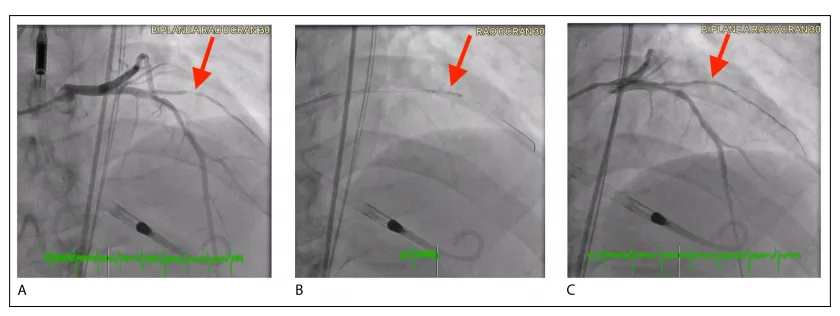

关于DCB治疗de novo小血管CAD疗效报告的不一致,以及多个试验结果的不一致,可能归因于不同DCB技术之间缺乏类效应,以及手术技术的差异,特别是病变准备不充分。例如,PICCOLETO(药物洗脱球囊治疗小冠状动脉血管疾病疗效)研究中相互矛盾的发现可以部分解释为大约75%的入组患者存在次优的病变预扩张。表2提供了DCB在de novo小血管冠状动脉疾病中的主要RCTs总结。图6和图7说明了我们成功应用AGENT DCB治疗de novo小血管CAD的案例。

图6 应用药物涂层球囊(DCB)治疗新发小血管病变的冠状动脉造影图像示意图(A) 术前图像显示第一对角支近端段存在90%狭窄。(B) 术中释放2.5 × 15 mm的AGENT药物涂层球囊,以8个大气压扩张60秒。(C) 术后图像显示DCB干预后狭窄显著改善,残留狭窄率为20%。